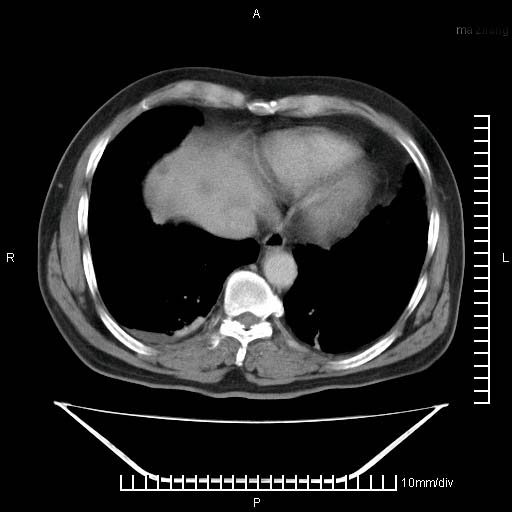

考虑右肺下叶周围癌肝转移

肝内多发转移瘤,右下肺炎症并少量胸水。胃壁增厚建议胃镜,胰尾部“病变”为肠管。

1)肝脏多发性转移瘤(不排除胰尾癌转移所致可能)。2)腹水。3)右侧少量胸腔积液。

右下胸膜肥厚。